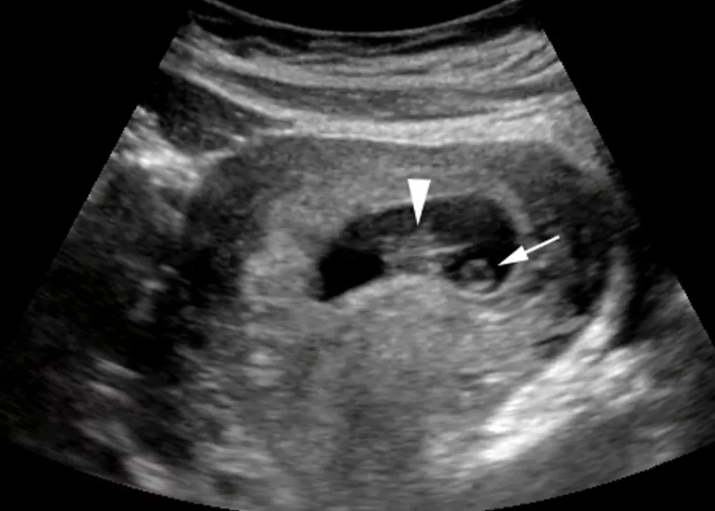

Это было около десяти лет назад, когда я ходила с животиком. В один день я проснулась с мыслью, что сегодня мне к врачу, и я наконец узнаю пол своего малыша. Чувствовала себя замечательно, и поводов для беспокойства не было. Однако, когда я повспоминала все, что было, то начала волноваться!